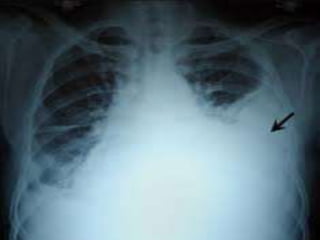

HEMOTHORAX

• Pathogenesis

- Haemothorax following a blunt or penetrating wound

to the chest can be caused by bleeding from any

structure in the thorax: the intercostal arteries, the

lung, the great vessels, or the heart.

• Clinical Features

- Initial findings include anxiety, dyspnea, tachypnea, and

tachycardia.

- Diminished breath sounds and dullness to percussion

are found over the affected hemithorax.

- Massive hemothorax can produce significant

hemodynamic instability secondary to hemorrhagic

shock.

• Diagnosis : By physical examination and CXR

• Treatment

- Place a chest tube.

- Findings of 1,500 mL of blood initially, or more than

200 mL/hour for 2 to 4 hours, generally mandate a

thoracotomy to control bleeding.

- Witnessing any loss of vital signs is an indication for

ED thoracotomy